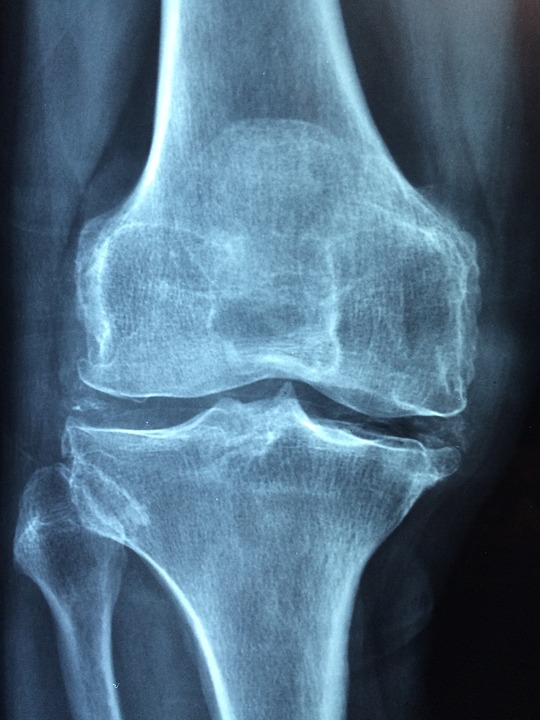

Traumatologia.-Rodilla.-detalle-publicada

Edad, factor a considerar en lesión de rodillas